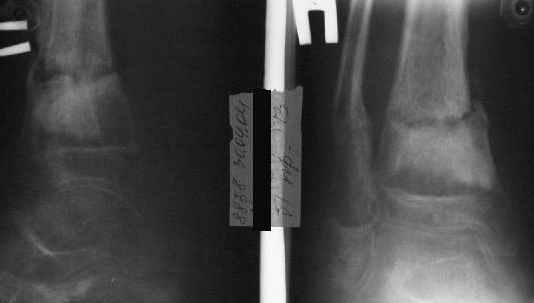

A> Операции: 1 Клиновидная резекция на вершине деформации м\берцовой кости.

A> 2 Тугоподвижный ложный сустав н\3 б\берцовой кости.

AVM> А каково у него укорочение голени?

В пределах 2 см.

Не катастрофа. Рост продолжается, будем следить в динамике.

Это сросшийся перелом малоберцовой кости. И ложный сустав

н\3 б\берцовой кости.

A> Это сросшийся перелом малоберцовой кости. И ложный сустав

A> н\3 б\берцовой кости.

Таперича это ясно.

А аппаратами пользуетесь?

Нашел в комп-ре схожий случай:

1) з/репозиция, 2) фиксация 2 спицами, 3) аппарат, 4) фиксационные

спицы удалены...

См. аттачт.

А можно было наложить аппарат и по поводу ложного сустава...

По крайней мере не было бы укорочения (пусть и в 2 см)...